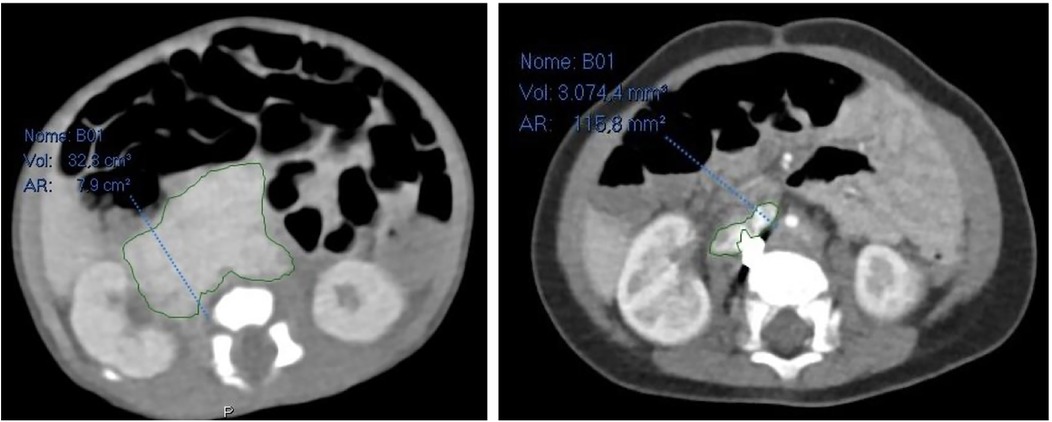

In order to better evaluate the vascularity and vessel proximity of the lesion, our oncologists suggested an abdominal MRI. An intralesional arteriovenous shunt was found in conjunction with a significant IVC dilatation brought on by hyperinflow (Figures 1, 2).

Figure 1. Dilated Inferior Vena Cava (IVC) on axial section at MRI.

Figure 4

CT scan images show two different cross-sections of the abdomen. The left image outlines a region with a volume of thirty-two point eight cubic centimeters and an area of seven point nine square centimeters. The right image outlines a smaller region with a volume of three thousand seventy-four point four cubic millimeters and an area of one hundred fifteen point eight square millimeters. Both sections are marked with green boundaries and blue annotations.

Figure 4. On the left abdominal CT scan at admission, on the right abdominal CT scan 6 months after embolization.